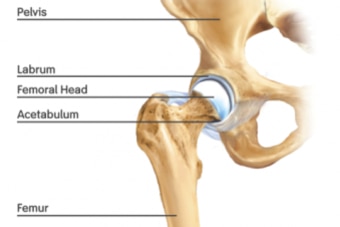

The "hip" marks the point where the femur (or thigh bone) meets the pelvis. Specifically, the rounded head of the femur sits within the cup-like acetabulum—or hip socket.

Around the rim of the acetabulum sits a cartilaginous labrum.

By encircling the acetabulum, the labrum deepens the cup inside which the head of the femur rests. As a result, the femur sits more snugly and is less able to fall out of the socket—a dislocation.

For a better picture, imagine a beach ball sitting inside an inner tube. The ball is the head of the femur, and the inner tube is the labrum.